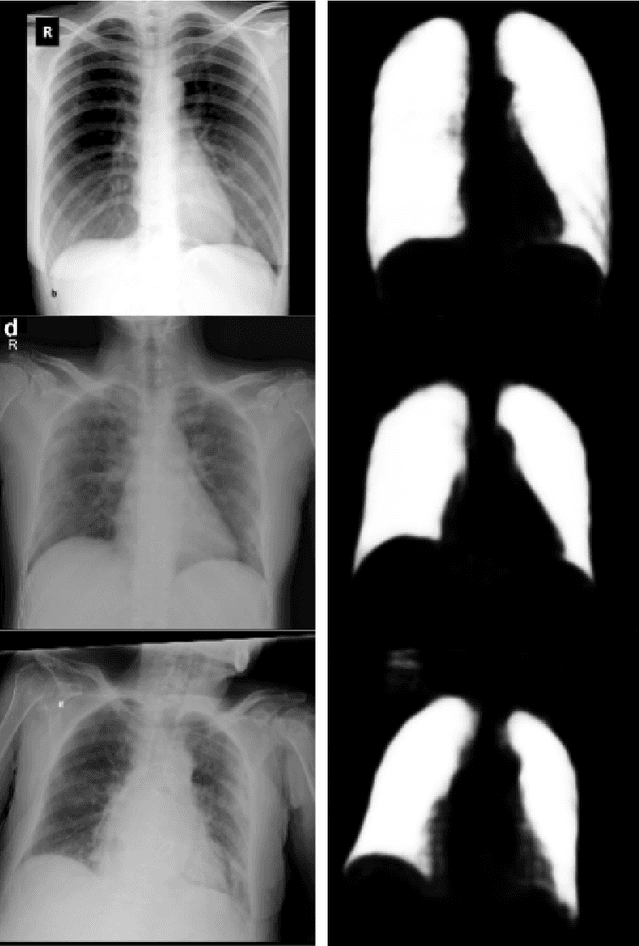

Abstract:This study presents a comparative analysis of methods for detecting COVID-19 infection in radiographic images. The images, sourced from publicly available datasets, were categorized into three classes: 'normal,' 'pneumonia,' and 'COVID.' For the experiments, transfer learning was employed using eight pre-trained networks: SqueezeNet, DenseNet, ResNet, AlexNet, VGG, GoogleNet, ShuffleNet, and MobileNet. DenseNet achieved the highest accuracy of 97.64% using the ADAM optimization function in the multiclass approach. In the binary classification approach, the highest precision was 99.98%, obtained by the VGG, ResNet, and MobileNet networks. A comparative evaluation was also conducted using heat maps.

Abstract:We evaluated the generalization capability of deep neural networks (DNNs), trained to classify chest X-rays as COVID-19, normal or pneumonia, using a relatively small and mixed dataset. We proposed a DNN architecture to perform lung segmentation and classification. It stacks a segmentation module (U-Net), an original intermediate module and a classification module (DenseNet201). We compared it to a DenseNet201. To evaluate generalization, we tested the DNNs with an external dataset (from distinct localities) and used Bayesian inference to estimate the probability distributions of performance metrics, like F1-Score. Our proposed DNN achieved 0.917 AUC on the external test dataset, and the DenseNet, 0.906. Bayesian inference indicated mean accuracy of 76.1% and [0.695, 0.826] 95% HDI with segmentation and, without segmentation, 71.7% and [0.646, 0.786]. We proposed a novel DNN evaluation technique, using Layer-wise Relevance Propagation (LRP) and the Brixia score. LRP heatmaps indicated that areas where radiologists found strong COVID-19 symptoms and attributed high Brixia scores are the most important for the stacked DNN classification. External validation showed smaller accuracies than internal validation, indicating dataset bias, which segmentation reduces. Performance in the external dataset and LRP analysis suggest that DNNs can be trained in small and mixed datasets and detect COVID-19.

Abstract:We present an image classifier based on the CheXNet and a transfer learning stage to classify chest X-Ray images according to three labels: COVID-19, viral pneumonia and normal. CheXNet is a DenseNet121 that has been trained twice, firstly on ImageNet and then, for classification of pneumonia and other 13 chest diseases, over a large chest X-Ray database (ChestX- ray14). The proposed network reached a test accuracy of 97.8% and, for the COVID-19 class, of 98.3%. In order to clarify the modus operandi of the network, we used Layer Wise Relevance Propagation (LRP) to generate heat maps, indicating an analytical path for future research on diagnosis.